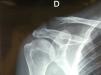

La media de la reincorporación a la actividad laboral fue completa en todos los casos a los 4,5 meses (rango de 2 a 9 meses). No se registraron secuelas ni incapacidad para realizar el trabajo previo al accidente. Todos, excepto uno de los pacientes, presentaban molestias durante la fisioterapia en abducción y antepulsión a partir de 90°, que desaparecieron al retirar la placa. Al paciente que no las presentó se le retiró la placa a las 12 semanas; uno de los objetivos de la retirada precoz era evitar las complicaciones consecutivas a la presencia del gancho. En 10 de los 11 casos no se dieron pérdidas de reducción tras la retirada de la placa. En el caso en que la hubo, fue parcial (fig. 3), en el último control radiográfico no había aumentado, no tuvo repercusión clínica ni retrasó la reincorporación del paciente a su actividad laboral.